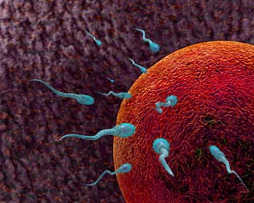

Reproductive Physiology

Duration : 4 hours 39 mins

Reproductive Physiology (BHMS)

Duration : 4 hours 39 mins